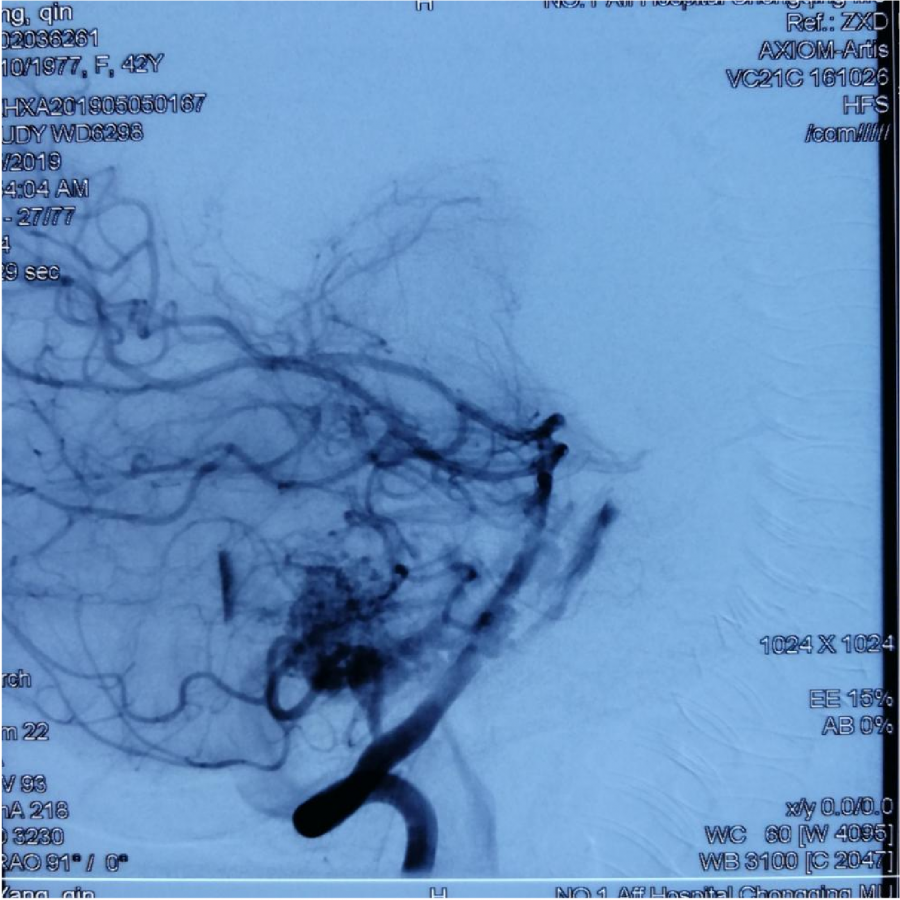

第⼀次DSA显⽰PICA供⾎

引流⾄⼄状窦

小脑后下动脉、小脑前下动脉参与供⾎

颈外动脉造影显⽰枕动脉参与供⾎